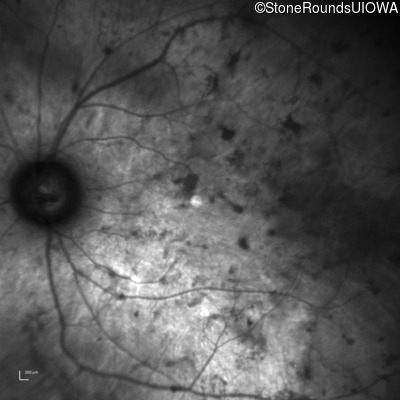

Infrared Fundus Photograph - Right - Light Perception

Exemplar